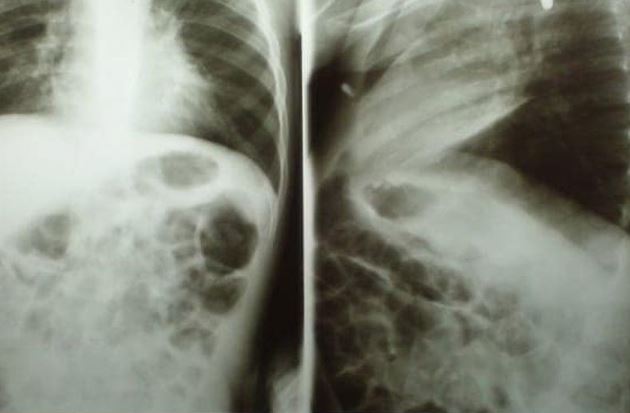

A 2-year-old boy, Dylan Alejandro has been hospitalized after swallowing a battery that exploded inside him.

The toddler swallowed the battery, which burnt his oesophagus, at his home in Cananea, Sonora State, north-western Mexico, last month.

His family hadn’t seen the incident take place, it was only when they notice him struggling to breathe that they took him to a local hospital, where they were told he had swallowed the battery.

Due to the severe nature of his injuries, the toddler was then transferred to another hospital in the state capital, Hermosillo.

Mum-of-eight Nayeli Guadalupe Coronado Nino, told local media how her son Dylan suffered an oesophageal burn and an infection in one of his lungs after the battery burst inside him.

He was admitted to intensive care on October 23, where medics said his blood was no longer processing oxygen.

Local media reported that surgeons can only operate on him when his oxygen levels are more stable.

Swallowing a lithium coin cell battery can cause a life-threatening chemical reaction within two hours – and proves fatal to at least two children a year.